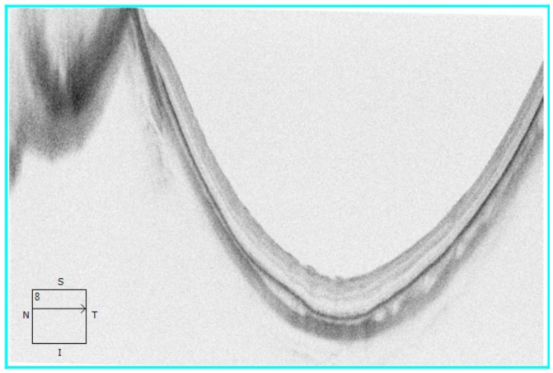

术后OCT